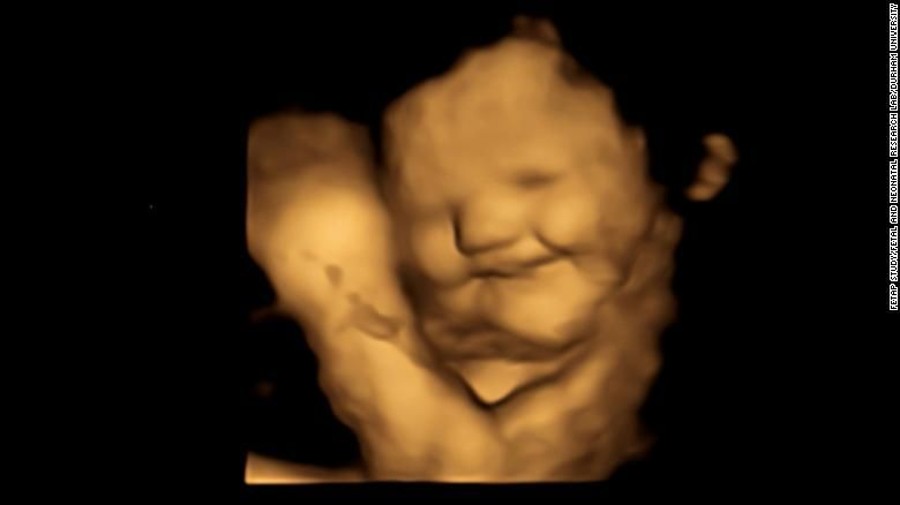

Fetos mudam expressão facial a partir de gosto dos alimentos